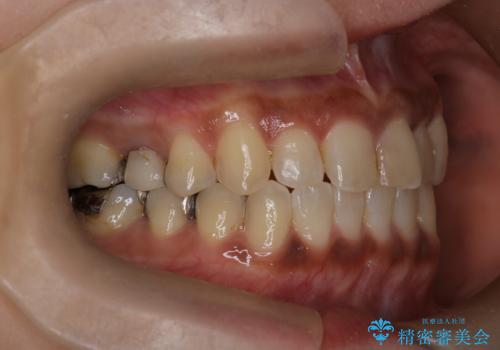

【インビザライン】前歯の凸凹をなおしたい

- 前歯の凸凹を主訴に来院されました。

インビザライン にて治療を行い、歯並びの改善を行うことができました。